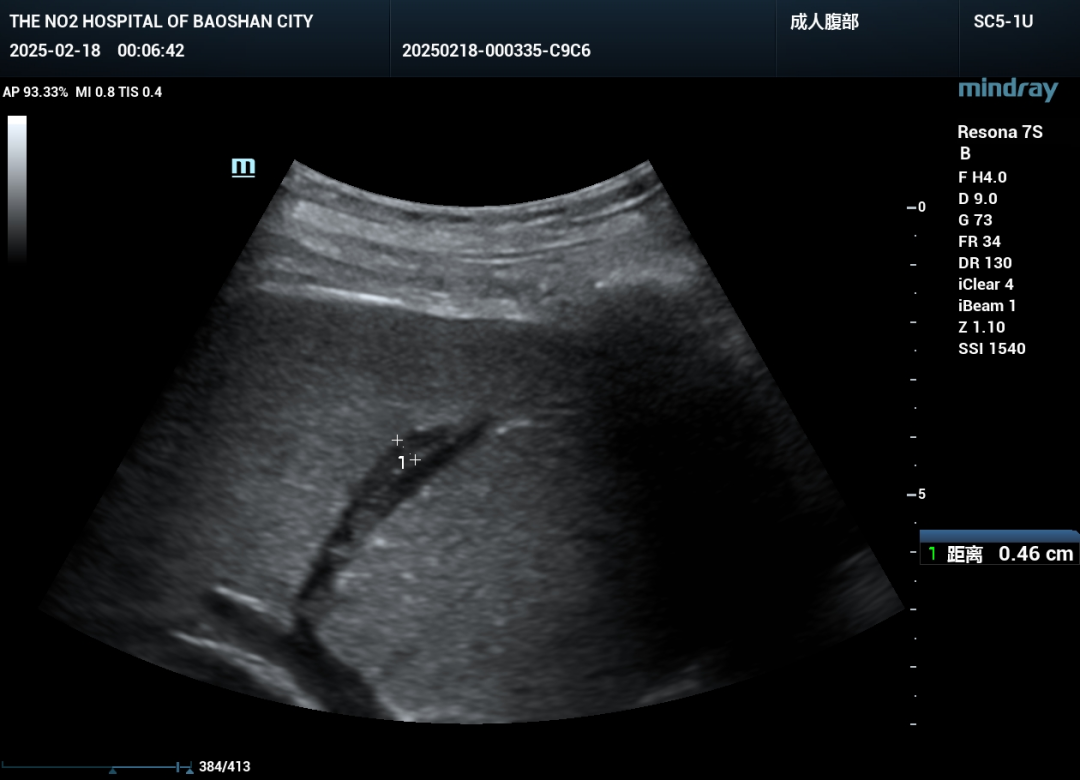

精心筹备后,决定命运的第一次PTCD手术正式开始。术中,凭借精湛的超声引导技术,陈贞奎主任手持穿刺针,稳、准、轻地经皮穿刺进入肝脏内扩张胆管,引入导丝,置入引流管、固定引流管,胆汁顺畅引出手术取得成功。

手术时,患者取仰卧位,这是最利于医生操作的体位。在超声引导下(保山二院超声医学科的超声引导技术非常出色,能清晰展示胆管及周围组织的结构),医生仔细确定穿刺点和穿刺路径,这一步对手术成败和患者安全至关重要。确定位置后,进行局部麻醉,减轻患者术中痛苦。随后,使用穿刺针经皮穿刺进入肝脏,再精准穿刺进入扩张的胆管。成功穿刺胆管后,引入导丝,沿导丝将引流管置入胆管合适位置,最后妥善固定引流管,确保胆汁能顺利引出,手术完成。